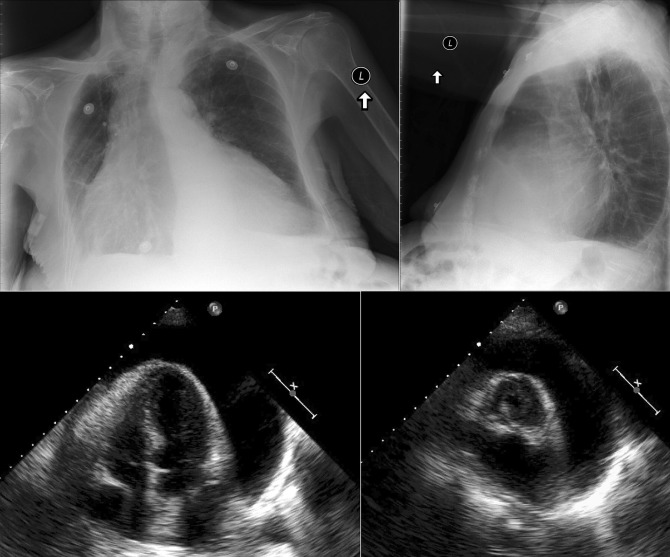

A prominent azygous vein, superior vena cava, or inferior vena cava suggests cardiac tamponade.

Echocardiography is the diagnostic test of choice for the evaluation of pericardial effusions. Pericardial tamponade remains a clinical diagnosis, strengthened by supportive echocardiographic findings.

In constrictive pericarditis ( Graphic 16-1 ; Figs. 16-16 to 16-23 ) , the CPS is usually nonspecifically and mildly enlarged. Occasionally, the heart is normal or small in size. The left atrium is the most frequently enlarged chamber, because its enlargement is less restricted by pericardium. The right atrial contour on the frontal chest radiograph may be flattened. Calcification of the pericardium suggests past tuberculosis, but since tuberculosis has become uncommon at most centers, 90% of cases of constrictive pericarditis are currently noncalcified. Calcification, especially diaphragmatic, is not specific for constrictive physiology; it may be seen in the absence of cardiac compression. The apical surface is less frequently calcified than the interventricular and atrioventricular grooves. The apex seldom calcifies prominently in constrictive pericarditis; this finding suggests a calcified apical aneurysm rather that constrictive pericarditis.